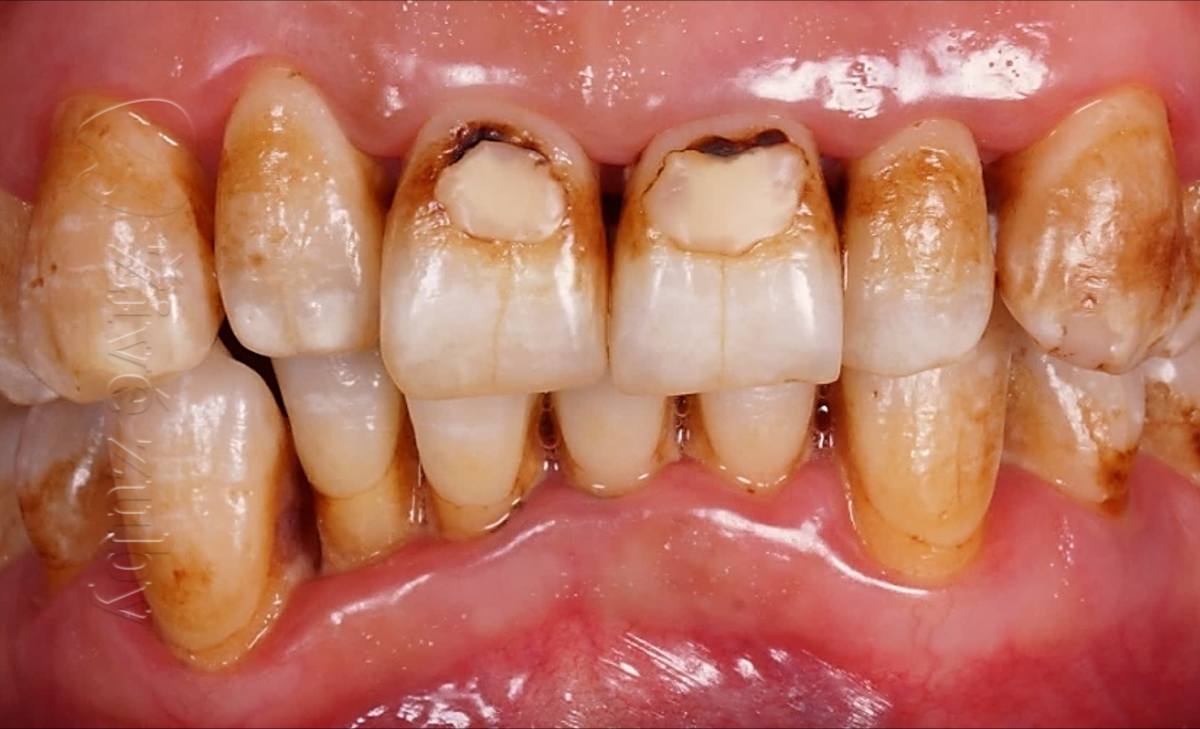

Mikroabraze a Infiltrace skloviny

(Ošetření Fluorózy a podobných lézí, demineralizaci skloviny, …)

Výchozí stav  ——- Kontrola po 2 letech